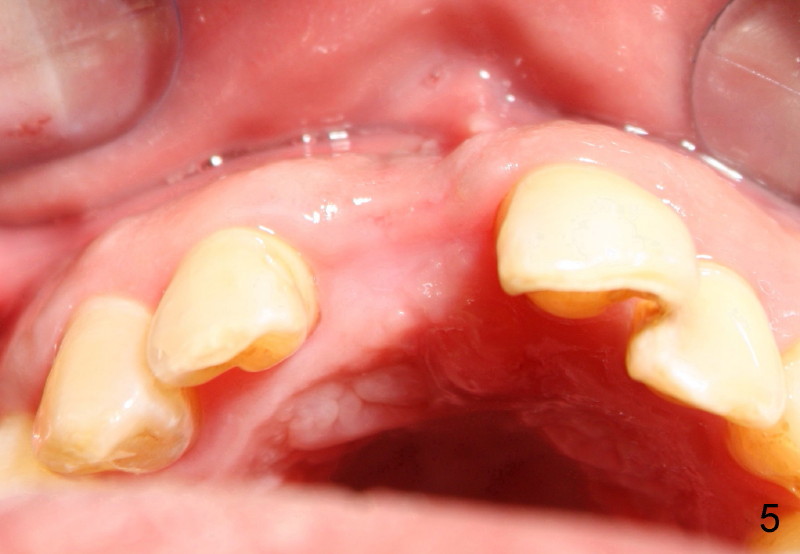

Fig.5 Two months after socket debridement, the wound appears to have healed with mild to moderate buccal plate atrophy, return to main article